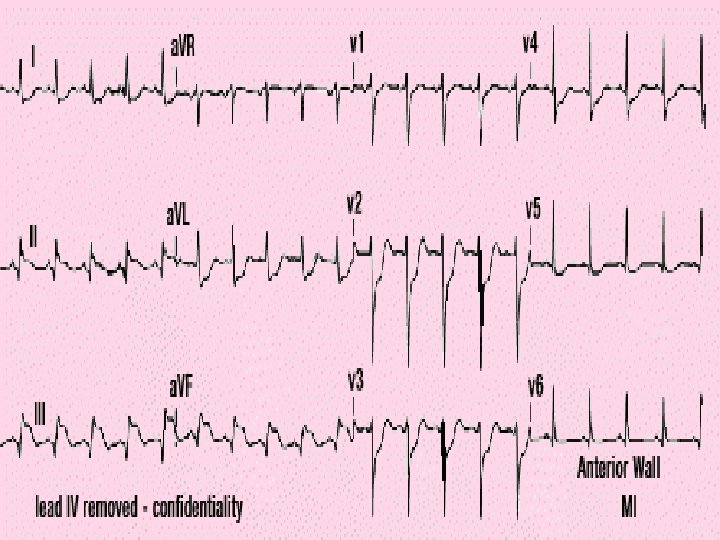

Conduction • Occurs approximately every 0. 8 seconds. • Electrical impulse can be recorded on an EKG • Used to detect abnormal activity or disease.